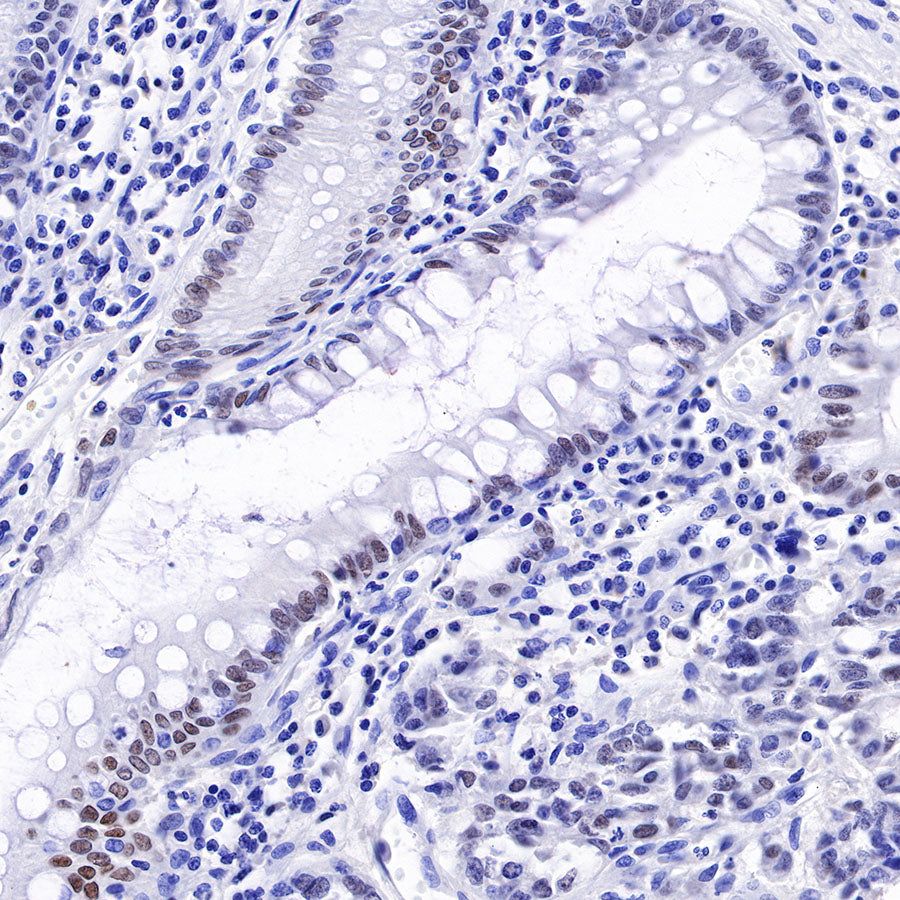

Immunohistochemistry

IHC shows positive staining in paraffin-embedded human kidney. Anti-HNF4α antibody was used at 1/500 dilution, followed by a HRP Polymer for Mouse & Rabbit IgG (ready to use). Counterstained with hematoxylin. Heat mediated antigen retrieval with Tris/EDTA buffer pH9.0 was performed before commencing with IHC staining protocol.